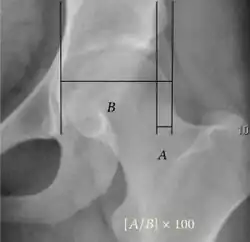

| Reimer's migration index[9] |

|

The percentage of the femoral head that lies outside of the acetabular roof. It is also called the femoral extrusion index. | <25% |